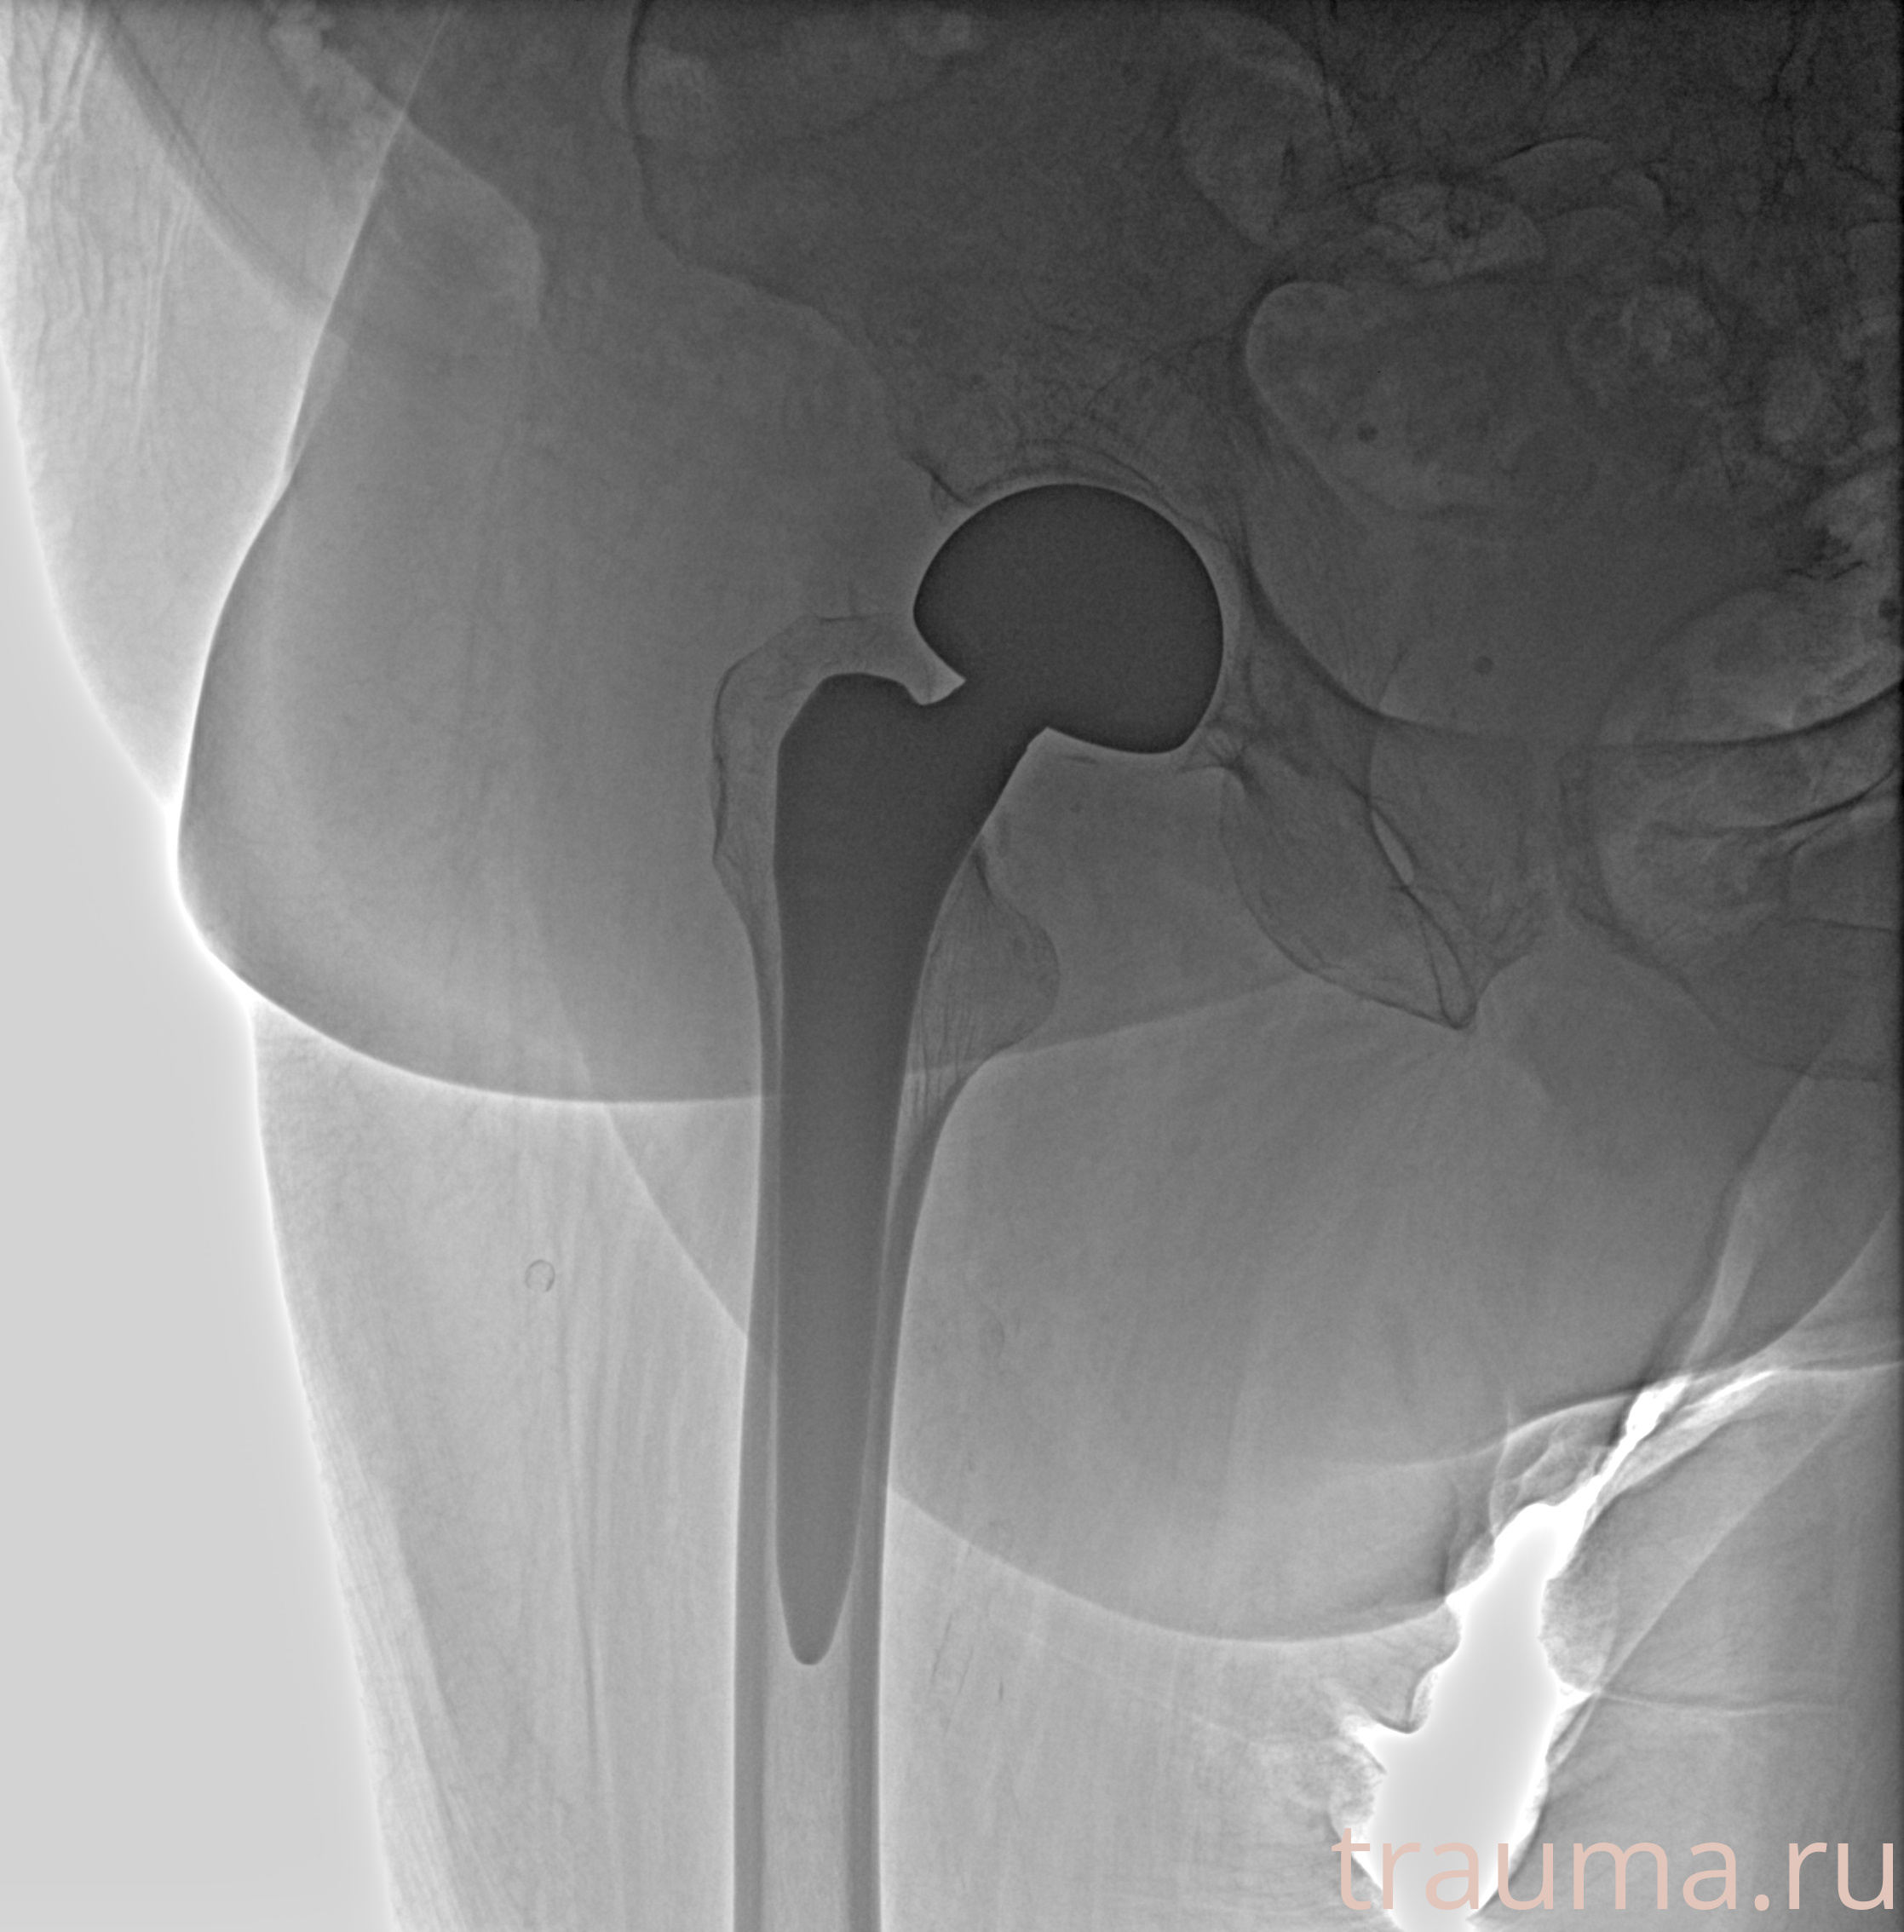

Рентгенограммы